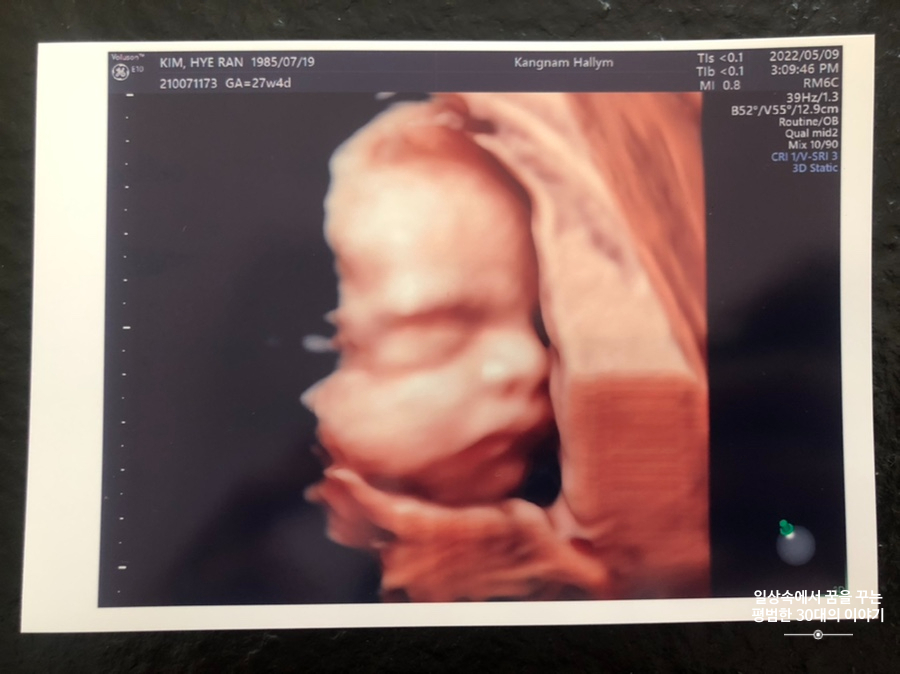

오늘은 입체 초음파 보는 날!!! 입체 초음파는 처음인데다 3주 만에 이안이 얼굴을 본다 생각하니 무척 설레는 마음으로 병원에 갔다. 첫 번째 시도에서는 계속 내 등 쪽으로 얼굴을 대고 엎드려 있어 실패! 초코우유 먹고 열심히 걸은 후, 30분 뒤에 다시 진행한 두 번째 시도에서는 얼굴 반쪽을 보여줬다. 얼굴 전면을 보지 못해 너무 아쉬웠지만 그래도 손가락 빨고 있는 모습, 웃고 있는 모습, 입 뻐끔 거리는 모습, 발차기 하는 모습, 손가락 쥐었다 폈다 하는 모습, 손을 휘적휘적 거리는 모습 등 다양한 모습을 보여줘서 그것만으로도 충분히 만족스러웠다. 내가 다니고 있는 강남성심병원은 입체 초음파가 다른 병원에 비해 무척 비싼 편인데(진료비 내역을 보니 초음파 진단료가 129800원 나옴) 그나마 위안을 삼을 수 있는 것은 화질이 그나마 좋은 편이라는 것이다.